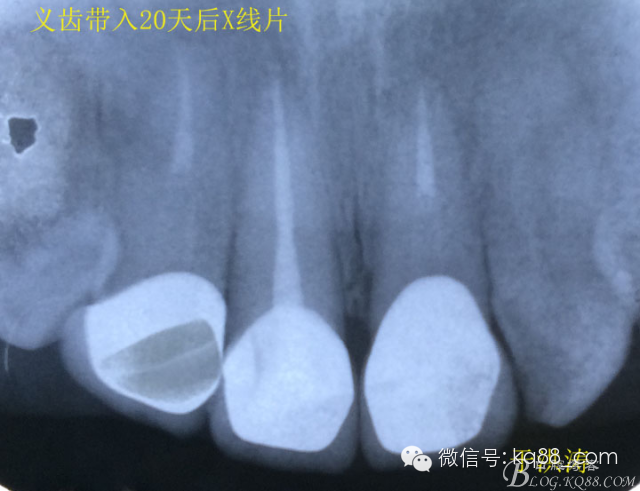

檢查:明顯可見22牙冠橫向斷裂至頸1/3處,近遠中與腭側斷裂至齦下??梢?/span>11牙冠斜向近中斷裂,近中與腭側均斷裂至齦下。21牙冠中1/3有裂痕。11 21 22松動(0),11 21叩(+),22叩(-),11 21 22探(-),11 21 22冷熱(-)。11 21 22唇側牙齦與粘膜和根尖相應部位未見明顯改變。11 22腭側牙齦增生性改變。11 21 22腭側粘膜和根尖相應部位未見改變。11 21 22舌側窩均有充填物。面部左右對稱無改變。余牙正常。(11,21,22牙冠顏色無改變)。 輔助檢查:X線片檢查11 22牙冠均有缺失。11 21 22 髓腔內均有充填物,11充填不到位, 21充填不實,22充填到位髓腔高密度影像。11 21 牙周膜有增寬,21根尖區(qū)有2mm左右低密度影像。未發(fā)現(xiàn)有牙根側穿或斷裂異物。 診斷:11,21慢性尖周炎,11,22殘冠。 治療計劃: 22無需治療。11 21 建議牙齒根管再治療。告知情況及費用。 1,11 21去除根充物。 2,11 21根管治療。 3,11 22纖維樁樹脂核修復。 4,高頻電刀去除11 22腭側牙齦組織到斷面。 5,11,21,22全瓷單冠修復牙齒。 治療過程:經(jīng)患者同意。H銼去除11 21原有充填物,未發(fā)現(xiàn)明顯滲出物,無異味。K銼疏通根管,VDW根測儀測量長度,11牙20mmWL,21牙20mmWL。S3鎳鈦器械預備根管。(全程1%次氯酸鈉沖洗EDTA溶解潤滑)試尖片顯示牙膠未到位,繼續(xù)向牙根尖各2mm進入預備。吸潮紙尖吸干根管,登士柏樹脂根充糊劑輸送至根尖部位,以測量數(shù)據(jù)用牙膠尖冷充側壓充填根管,3M玻璃離子封閉根管口。不可用患牙啃咬硬物,擇日冠修復。 輔助檢查:插針X線片顯示根管內充填物已經(jīng)取出。試尖片顯示牙膠尖未到位,繼續(xù)用K銼和機括向根尖預備。根充結束片顯示根充密實,無超充,無欠充。 醫(yī)囑:常規(guī)醫(yī)囑,不適隨診。 各步驟操作見下圖 于洪濤 2015.02.03 復 診 主訴:無疼痛,不適癥狀已經(jīng)消失。 檢查:11 21 充填物存在邊緣封閉完好,叩(-)松動(0)牙齦及周圍同初診。11 21 22無任何不適。 治療過程:由于患者自身原因即將兩個月來復診。拍X線片,去除11 22髓腔內部分牙膠,P鉆預備根管到達預定位置。粘結纖維樁,制作冠核。初預備11 21 22牙冠。高頻電刀按廠家要求功率和方法去除11 22腭側牙齦組織到達牙齒斷裂部位,調整檔位和功率繼續(xù)凝固和精修腭側組織,11 21 22排齦精修拋光。硅橡膠兩次法取模,可見模型完整肩臺清晰。制作臨時冠,科爾不含丁香油臨時冠粘結系統(tǒng)粘接。 模型送技師制作。預約義齒佩戴時間。(需術前牙齒比色) 輔助檢查:X線片顯示根尖低密度影像消失,牙周未見異常。X線片顯示纖維樁密合到位。 醫(yī)囑:不可用臨時牙肯咬硬物,不適隨診。 各步驟操作見下圖 于洪濤 2015.03.26 復 診 主訴:牙齒無癥狀,自感腭側術區(qū)舌舔粘膜不適。 檢查:臨時冠完整,無松動,邊緣緊密。牙齒無疼痛,唇側牙齦無明顯紅腫,腭側牙齦愈合良好,牙冠肩臺邊緣清晰。腭側牙齦術區(qū)中度觸及有少量滲血。 治療過程:義齒制作完成。去除臨時冠及粘結物。義齒試戴調整完全就位,無懸突,無縫隙。清洗義齒,氫氟酸處理義齒50秒(加強醫(yī)患防護),沖洗吹干,偶聯(lián)劑處理備用。基牙37%酸處理15秒,沖洗吹干,隔濕,排齦,涂第五代粘結劑。小蜜蜂雙固化樹脂水門汀激活攪拌注入義齒中,按順序就位,加壓力,牙線去除牙縫隙多余樹脂,涂阻氧劑,基牙唇腭側各光照固化3秒之后去除多余水門汀取出排齦線,繼續(xù)光照固化牙齒每個面20秒。精細查找去除多余水門汀。 醫(yī)囑:1,患牙咀嚼硬物加以注意。 2,常規(guī)醫(yī)囑,不適隨診,。 3,加強口腔衛(wèi)生意識。定期復診檢查。 各步驟操作見下圖 于洪濤 2015.04.07 回訪病例 主訴:咀嚼食物非常自如,無任何不適。 檢查:義齒牙體完整。無松動,無叩痛。唇側牙齦紅潤質韌無萎縮,腭側術區(qū)牙齦愈合良好,無炎癥改變。唇腭側根尖相應部組織無改變。余牙正常。 輔助檢查:X線片顯示牙根及周圍未見異常。未見骨萎縮。牙冠及頸部未見異常。 醫(yī)囑:定期檢查義齒,不適隨診。 各步驟操作見下圖 于洪濤2015.04.28